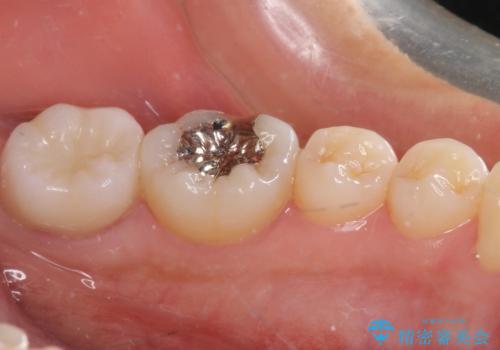

奥歯が痛い 保険治療後に症状が発現した歯のむし歯治療

2歯ともに根管治療を行い、その後はオールセラミッククラウンにて補綴治療を行うこととしました。

来院時には食事が取れないほどの痛みを訴えていらっしゃいましたが、処置後からは痛みが軽減され、食事もいつも通りに取れるようになりました。